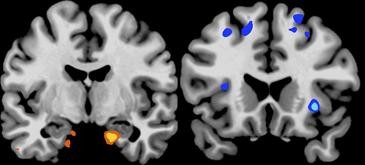

“Nuestros resultados han demostrado que las regiones del cerebro relacionadas con la toma de decisiones de alto nivel quedan embotadas por la falta de sueño a la hora de elegir alimentos. Por el contrario, las estructuras profundas del cerebro que controlan la motivación y el impulso se amplifican”, dice el investigador.

Walker indica que esta menor actividad cerebral en regiones que controlan las buenas decisiones, en combinación con la amplificación en aquellas más relacionadas con la recompensa inmediata, encaja bien con las teorías de que la falta de sueño favorece el aumento de peso y la obesidad